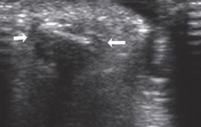

Acute phase of foreign body

Foreign body present < 3 days

Immediately after injury → air or dirty shadowing

24 hrs after injury → hypoechoic ring/halo develops